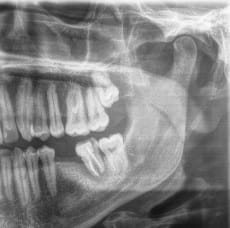

Adjunto orto.